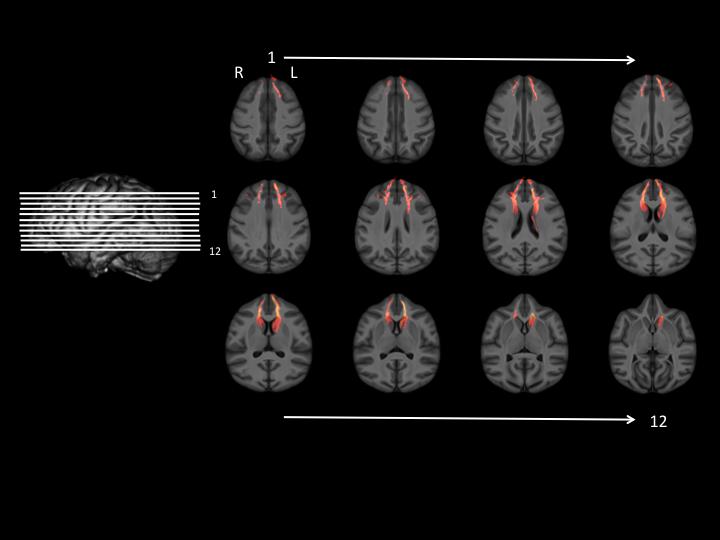

This study provides the first evidence in primates, including humans, of an association between delay of gratification performance and white matter connectivity between the caudate and the dorsal prefrontal cortex in the right hemisphere, said Dr. Robert Latzman, assistant professor in the Department of Psychology at Georgia State, who led the study with Dr. William Hopkins, professor of neuroscience at Georgia State.

The researchers found higher white matter connectivity between the caudate and dorsal prefrontal cortex in the right hemisphere of the brain was associated with the learning of delay of gratification.

All chimpanzees received DTI (diffusion tensor imaging) brain scans during their annual physical examination. Data were acquired that allowed the researchers to examine white matter tracts, or bundles of neurons that connect one part of the nervous system with another, between the caudate and prefrontal cortex. The white matter connectivity between these brain structures was compared to the chimpanzees' delay of gratification abilities.